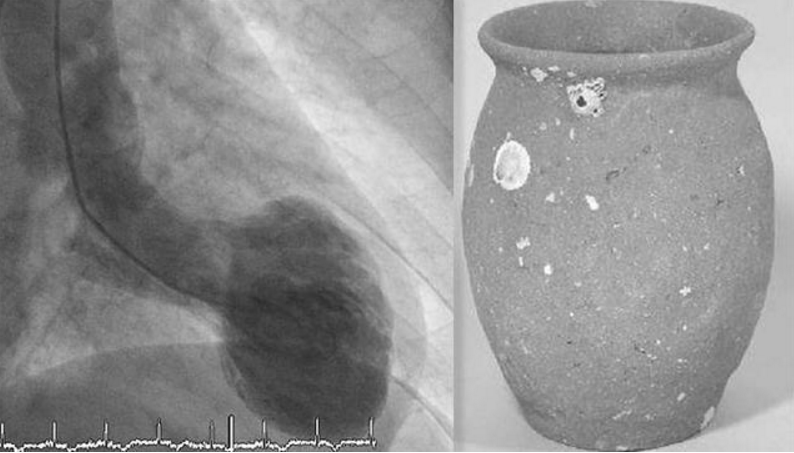

1990年有日本学者描述一种“章鱼壶心肌病(Takotsubo cardiomyopathy)”。此病因发作时左心室心尖呈气球样与传统日本章鱼鱼篓的圆形底部和窄口相似而命名(称为Takotsubo章鱼壶)。

因病人心脏的交感神经受体在左心室基部与心尖部位的比例不一樣,当患者极度伤心、遭逢压力应激、惊吓或疼痛時,就会造成心尖未收縮,但心室基部强力收缩如气球的情形(如下图A心尖呈球形;B为心室正常收缩)。

其发病时胸痛、心电图ST段抬高和心肌酶水平升高,与急性心肌梗死的表现是一致的。但当患者行冠状动脉血管造影术时,可发现无显著冠状动脉狭窄,而左心室造影显示左心室心尖部存在球样扩张。